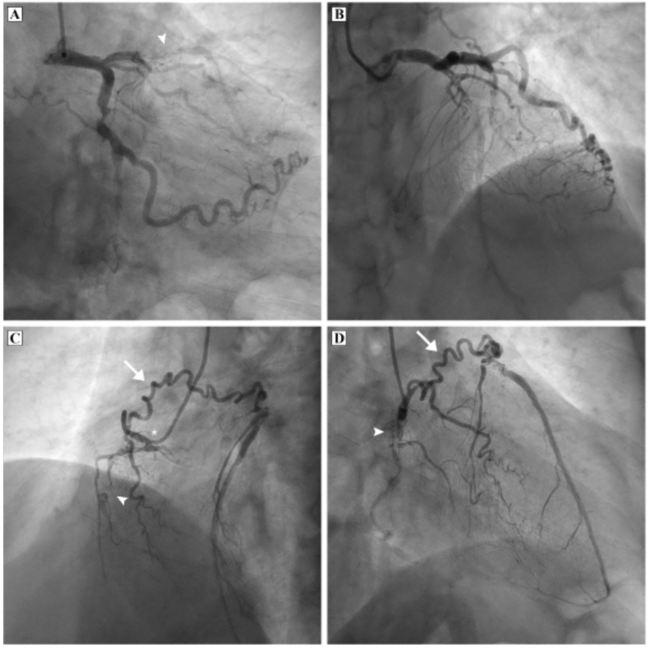

A 63-year-old male patient presented with angina for 6 months with recent aggravation of symptoms. Physical examination was unremarkable. The electrocardiogram was within normal limits, cardiac troponin levels were not elevated, and left ventricular function was normal. Due to recent worsening of symptoms, we performed a coronary angiogram. It revealed severe triple vessel disease with chronic total occlusion (CTO) of the proximal left anterior descending (LAD), 90% obstruction of the proximal circumflex with CTO of the distal circumflex, and 99% occlusion of the proximal right coronary artery (RCA). The conus artery had a separate origin and provided collateral blood supply to the entire LAD territory by the Vieussens’ arterial ring (Figure 1 and Video 1). We recommended coronary artery bypass grafting.

The Vieussens’ artery is an anastomotic communication between the conus branch of the RCA and the LAD. Vieussens’ ring is so named because it circles around the great vessels in the form of a partial ring. The course of the artery can be best understood in 2 orthogonal views. In the left oblique view, the artery appears coursing upward to the left. In the right oblique view, it courses anteriorly across the right ventricular outflow tract.

The clinical significance of Vieussens’ arterial ring lies in it being a major source of collateral blood flow to an occluded LAD. The presence of this large collateral may explain preserved ventricular function in our patient, despite severe triple-vessel disease. A significant proportion of patients with total occlusion of the LAD have prominent collateral flow from the conus. However, in nearly half of the general population, the conus branch arises directly from the aorta. Hence, selective engagement may be necessary to demonstrate retrograde filling of the LAD. The origin of the conus artery is anterior and superior to the RCA ostium and it can be engaged by slight withdrawal and counter-clockwise rotation of the catheter. Selective engagement is easier to perform with the Tiger catheter (Terumo) because of the upward bias of its tip. Precaution should be taken to monitor pressure waveform for the presence of wedging and to avoid forceful contrast injection into the conus, which can result in injury to the vessel. Prolonged contrast injections into the conus predispose to ventricular fibrillation. The presence of a side hole in the Tiger catheter allows opacification of the adjoining RCA and makes contrast injection relatively safe.